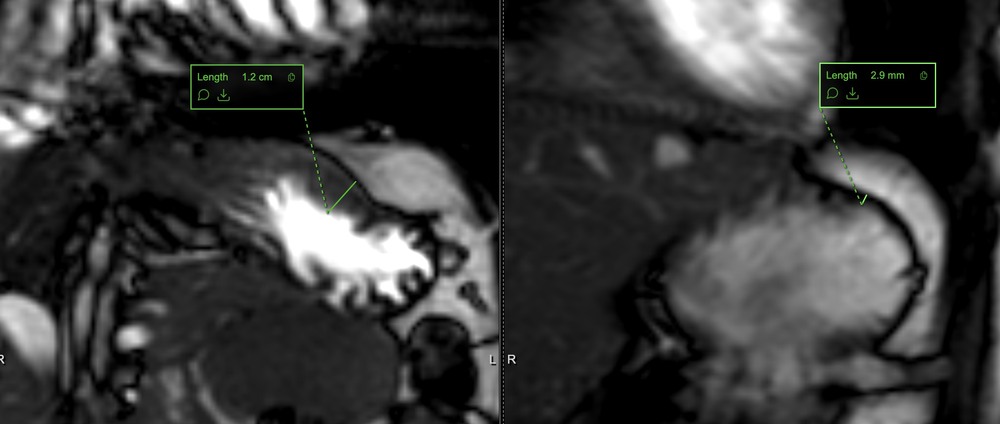

Fundus wall thickness and total gastric wall volume pre- and post-meal as a proxy of accommodation.

Gastric wall before (left) and after (right) a water challenge.